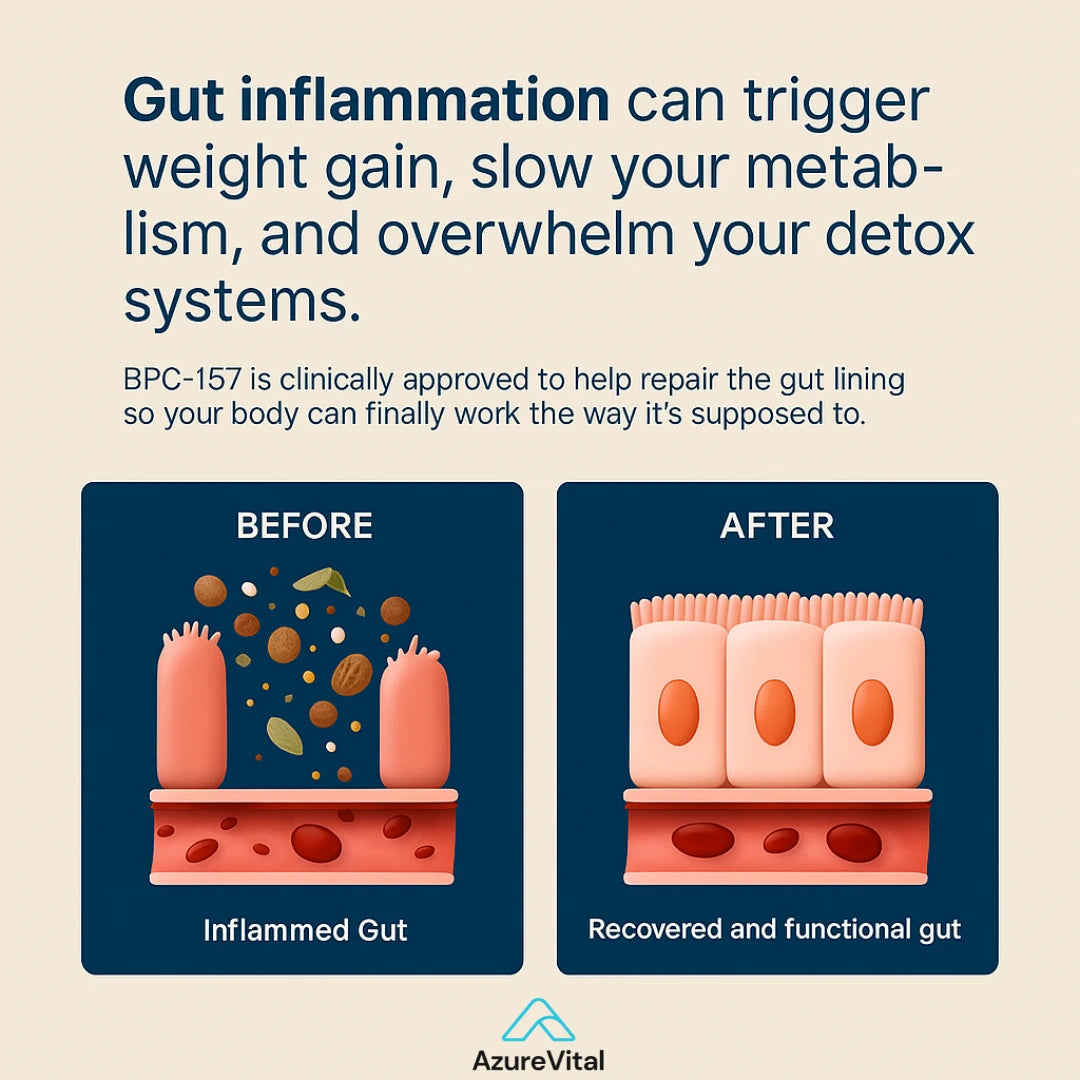

BPC-157 is a synthetic peptide derived from a natural protein found in the human stomach.

Known for its regenerative properties, BPC-157 has gained attention for its potential to support wellness, helps with inflammation, and support recovery in muscles, joints, and connective tissue.

Originally studied for its role in gut protection, it is now widely used by athletes and biohackers for its broad systemic benefits.

Injuries cause micro-tears and inflammation that restrict blood flow and delay recovery.

BPC-157 identifies injured tissue and triggers targeted healing by improving blood flow and nutrient delivery.

Tendons, muscles, and joints recover faster—restoring movement and reducing pain naturally.